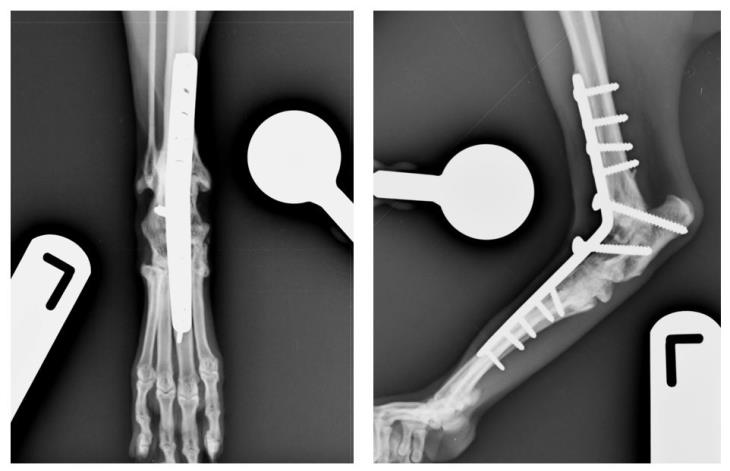

Full recovery can take several months and this depends on the rate of bone healing and other factors. Fusion of the joint was documented radiographically 2 months postoperatively as seen in the radiographs below.